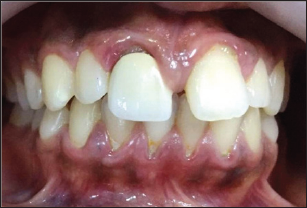

A 19year old female reported to New Al zahir Dental Clinic with chief complaint of unaesthetic appearance and pain in previously treated right upper front tooth. She gave a history of trauma 8 years ago, due to fall in house while playing with siblings and the fractured tooth segment was lost. The tooth was asymptomatic but observed tooth discoloration after 14 days of trauma. She was concerned for unaesthetic appearance and discoloration of tooth. Hence, undergone treatment by the family dentist, where pulpotomy was performed followed by aesthetic composite restoration. She was not pleased with composite restoration hence; a metal ceramic crown was provided for esthetic satisfaction. She does not recollect any sort of vitality testing done previously. She had observed an increase in gap between crown and gingiva in the first four years after placement of crown, then after its static. She is getting pain in the same tooth since 2 weeks. Clinical examination revealed, red edematous gingiva, accelerated gingival recession with round and thick gingival margin around maxillary right central incisor (Figure 1). Thermal and electric pulp testing revealed non-vitality for maxillary right central incisor. Radiographic investigation revealed an attempt for cervical pulpotomy was made but ended up presenting a periapical lesion having restricted root formation with an open apex (Figure 2).

Figure 1.